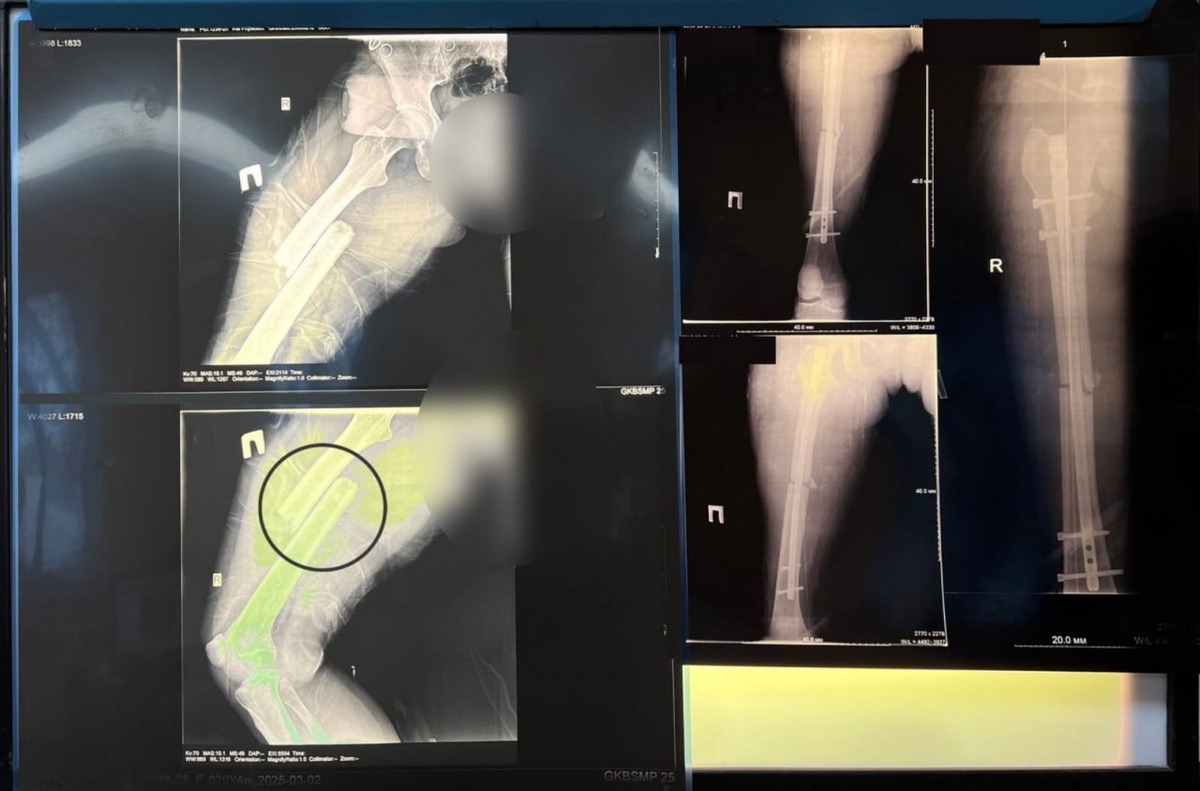

Как сообщили в региональном комитете здравоохранения, в начале марта бригада скорой помощи доставила пациентку в тяжелейшем состоянии. У девушки были диагностированы закрытая черепно-мозговая травма, открытый перелом средней трети бедренной кости со смещением и перелом в области тазовых костей.

«Это опасное и тяжелое повреждение опорно-длительного аппарата. Травма сопровождается обильным кровотечением из отломков костей и мягких тканей, травматическим шоком на фоне кровопотери и интенсивного болевого синдрома. В случае открытого перелома риск для жизни значительно увеличивается», – отметили в профильном комитете.

Для восстановления волгоградки была настроена система скелетного вытяжения. После была проведена операция по сопоставлению бедренной кости. Технологии позволили выполнить вмешательство с минимальной кровопотерей.